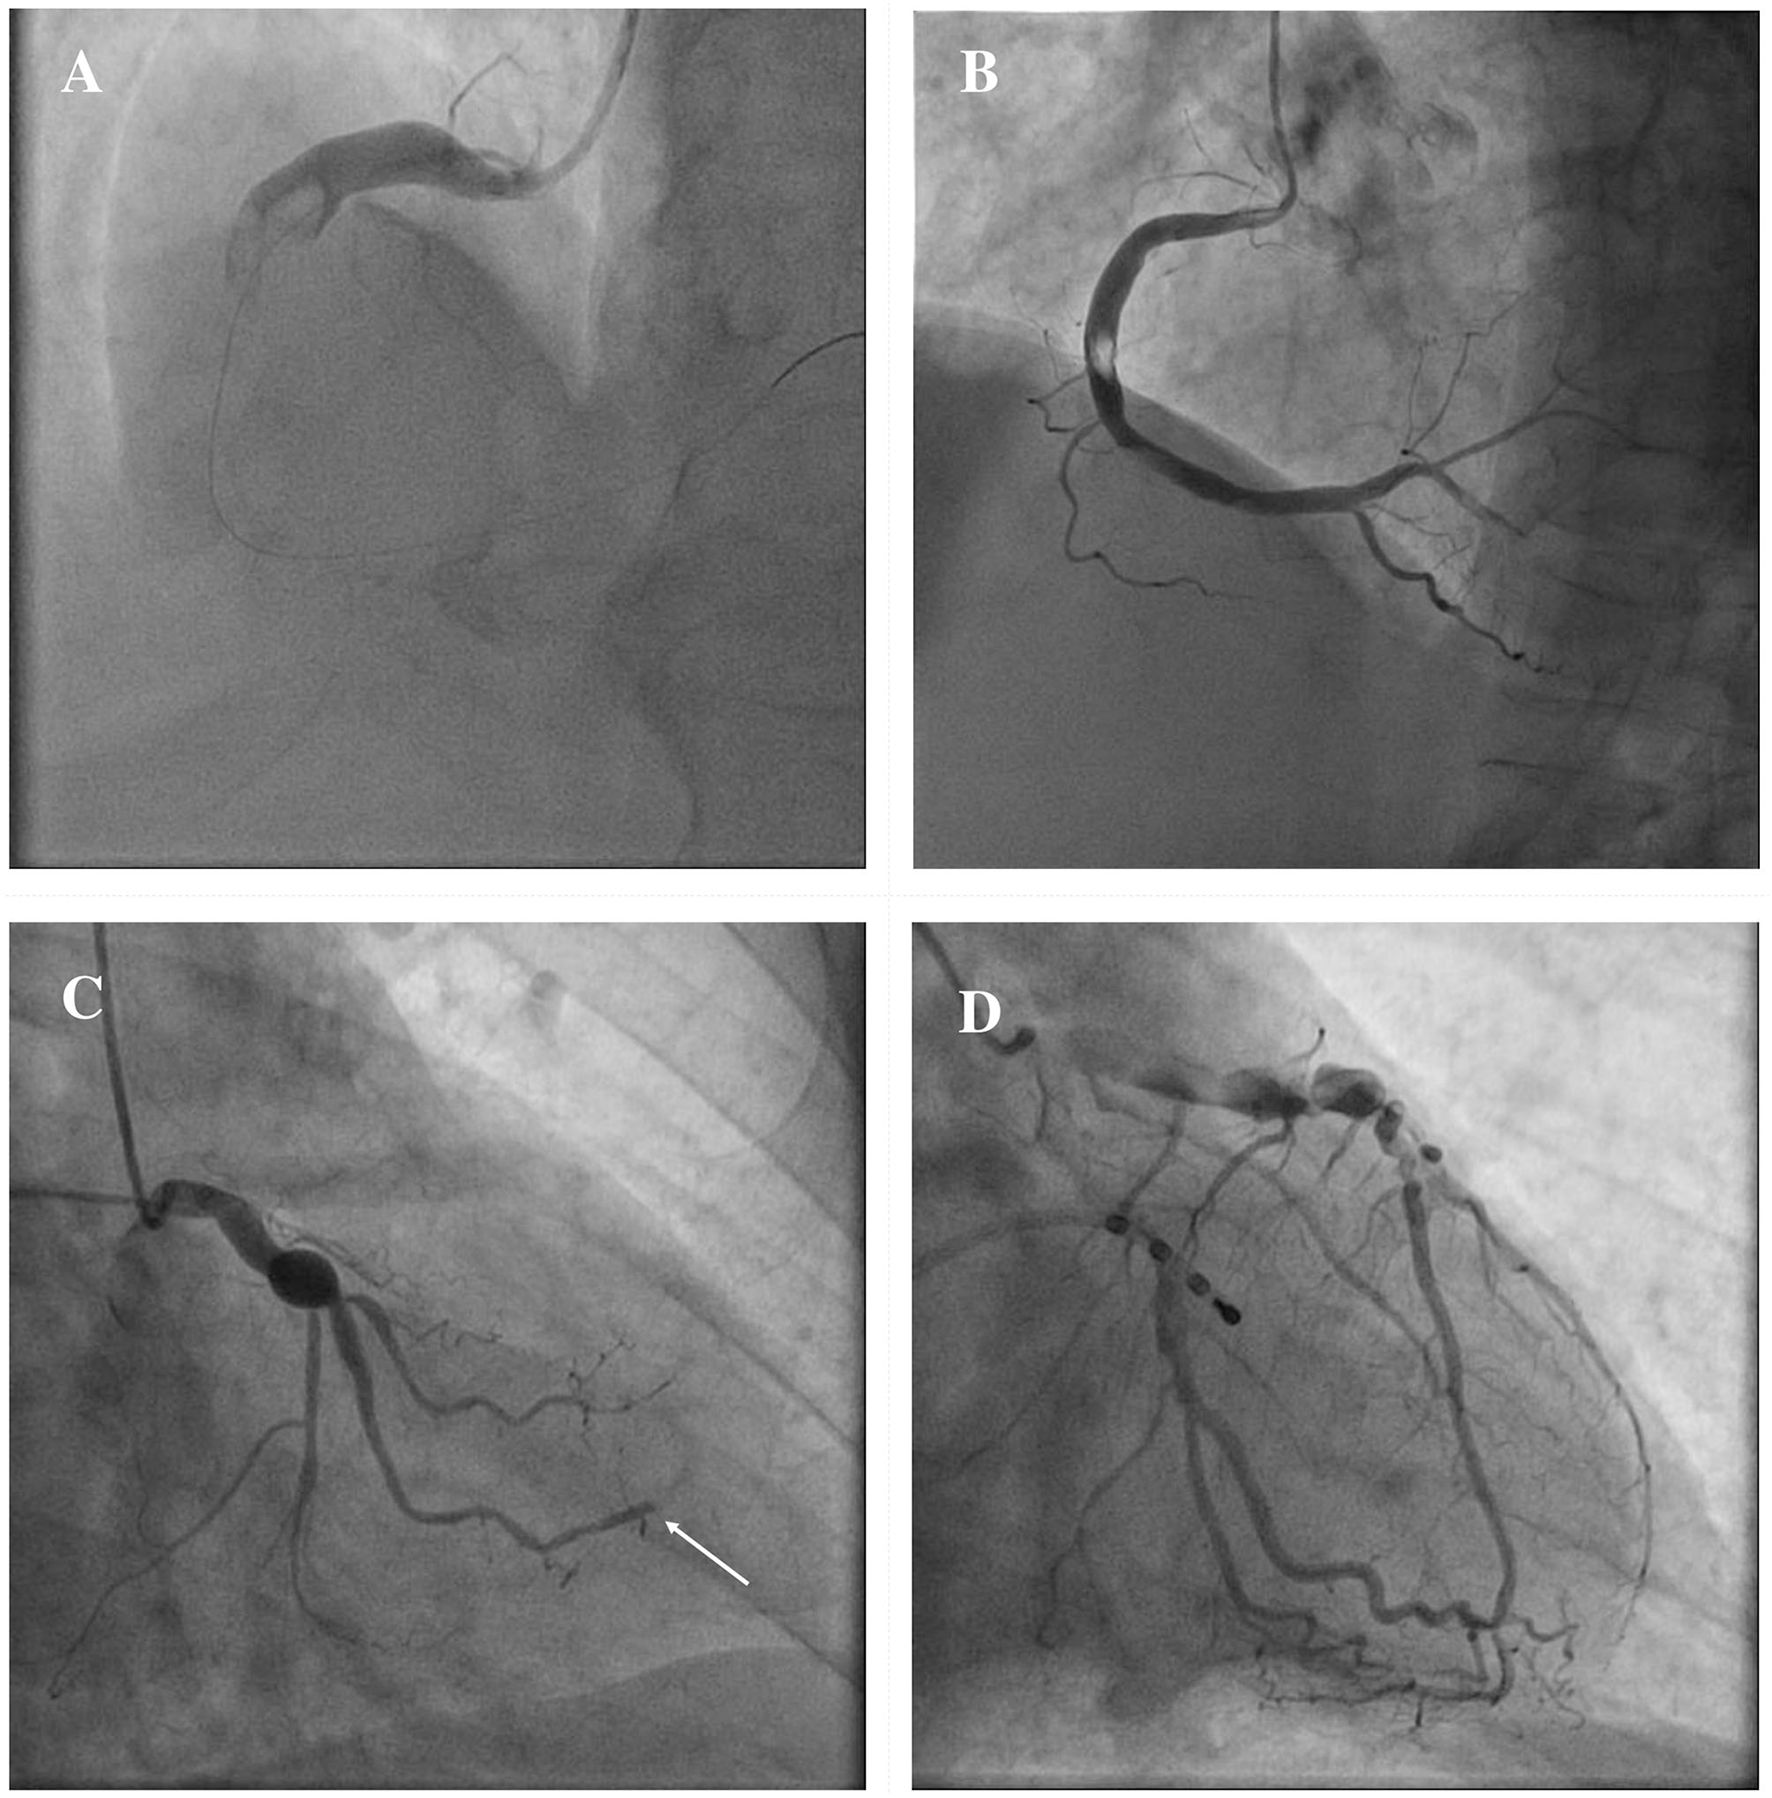

The clinical manifestations of CAE are heterogeneous, and often it is occasionally recognized during coronary angiography or computed tomography (CT). However, CAE may become clinically overt through different possible scenarios, including ACS, effort angina, exercise-induced ischemia, microvascular dysfunction, compression of adjacent cardiac or non-cardiac structures and the tragical, albeit rare, complication of rupture with acute cardiac tamponade (5, 58–60). In patients with CAE, there are several possible mechanisms leading to the clinical event of an ACS: (1) atherosclerotic plaque instability with high thrombus burden; (2) endoluminal thrombosis due to flow disturbances and blood stasis, in absence of underlying atherosclerotic lesions; (3) distal embolization of thrombotic material; (4) impairment of myocardial perfusion related to the severe slow flow, which can be clinically expressed either as ACS or effort angina. Figure 3 illustrates the main mechanisms of ACS in patients with CAE.

Figure 3

Mechanisms of ACS in patients with CAE. ACS in patients with CAE can occur through different pathophysiological mechanisms. Catastrophic plaque rupture resulting in acute vessel occlusion due to a huge thrombotic burden untreatable despite a timely primary PCI (A). Relevant filling defect due to endoluminal thrombus without significant underlying atherosclerotic plaque, to be ascribed to flow disturbances in an entirely ectatic RCA (B). Abrupt flow occlusion of the distal segment in a marginal branch (arrow) due to the embolization of clot fragments coming from a proximal saccular CAA of the LCx (C). Ectatic LAD showing images of advanced flow disturbances angiographical pattern, that suggest the relationship between impaired blood progression and myocardial ischemia (D). ACS, Acute Coronary Syndrome; CAA, coronary artery aneurysm; CAE, Coronary Artery Ectasia; LAD, left anterior descending; LCx, left circumflex; PCI, percutaneous coronary intervention; RCA, right coronary artery.